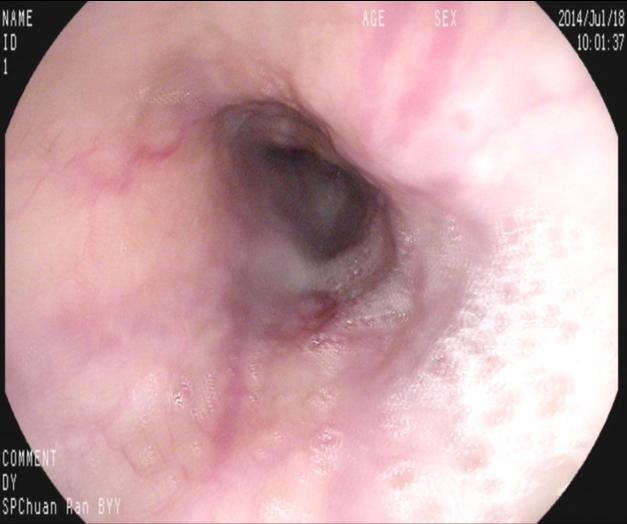

上2圖為重度曲張的食管靜脈,見(jiàn)紅色征較重。無(wú)活動(dòng)出血,顯然內(nèi)科止血治療有效。如果無(wú)積極有效的醫(yī)學(xué)干預(yù)再次出血率幾乎為100%,只是時(shí)間問(wèn)題,在受到食物磨擦,胃酸刺激、情緒波動(dòng)及自然病情變化等隨時(shí)有再出血可能,出現(xiàn)黑便甚至嘔血而危及生命,反復(fù)費(fèi)用也較高,再出血率也。

上2圖為套扎治療過(guò)程中。